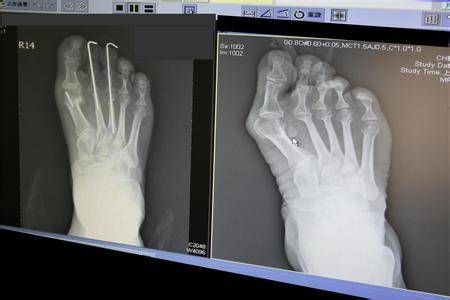

在2011年时,贝嫂就因非常严重的大脚趾外翻,

被专业医生要求放弃高跟鞋,但是她没有听。

大脚趾外翻不仅影响美观,而且会持续疼痛,严重的时候无法走路,如果去做手术矫正,即使手术成功,也留下了难看的疤痕,在那之后只能穿厚底鞋。